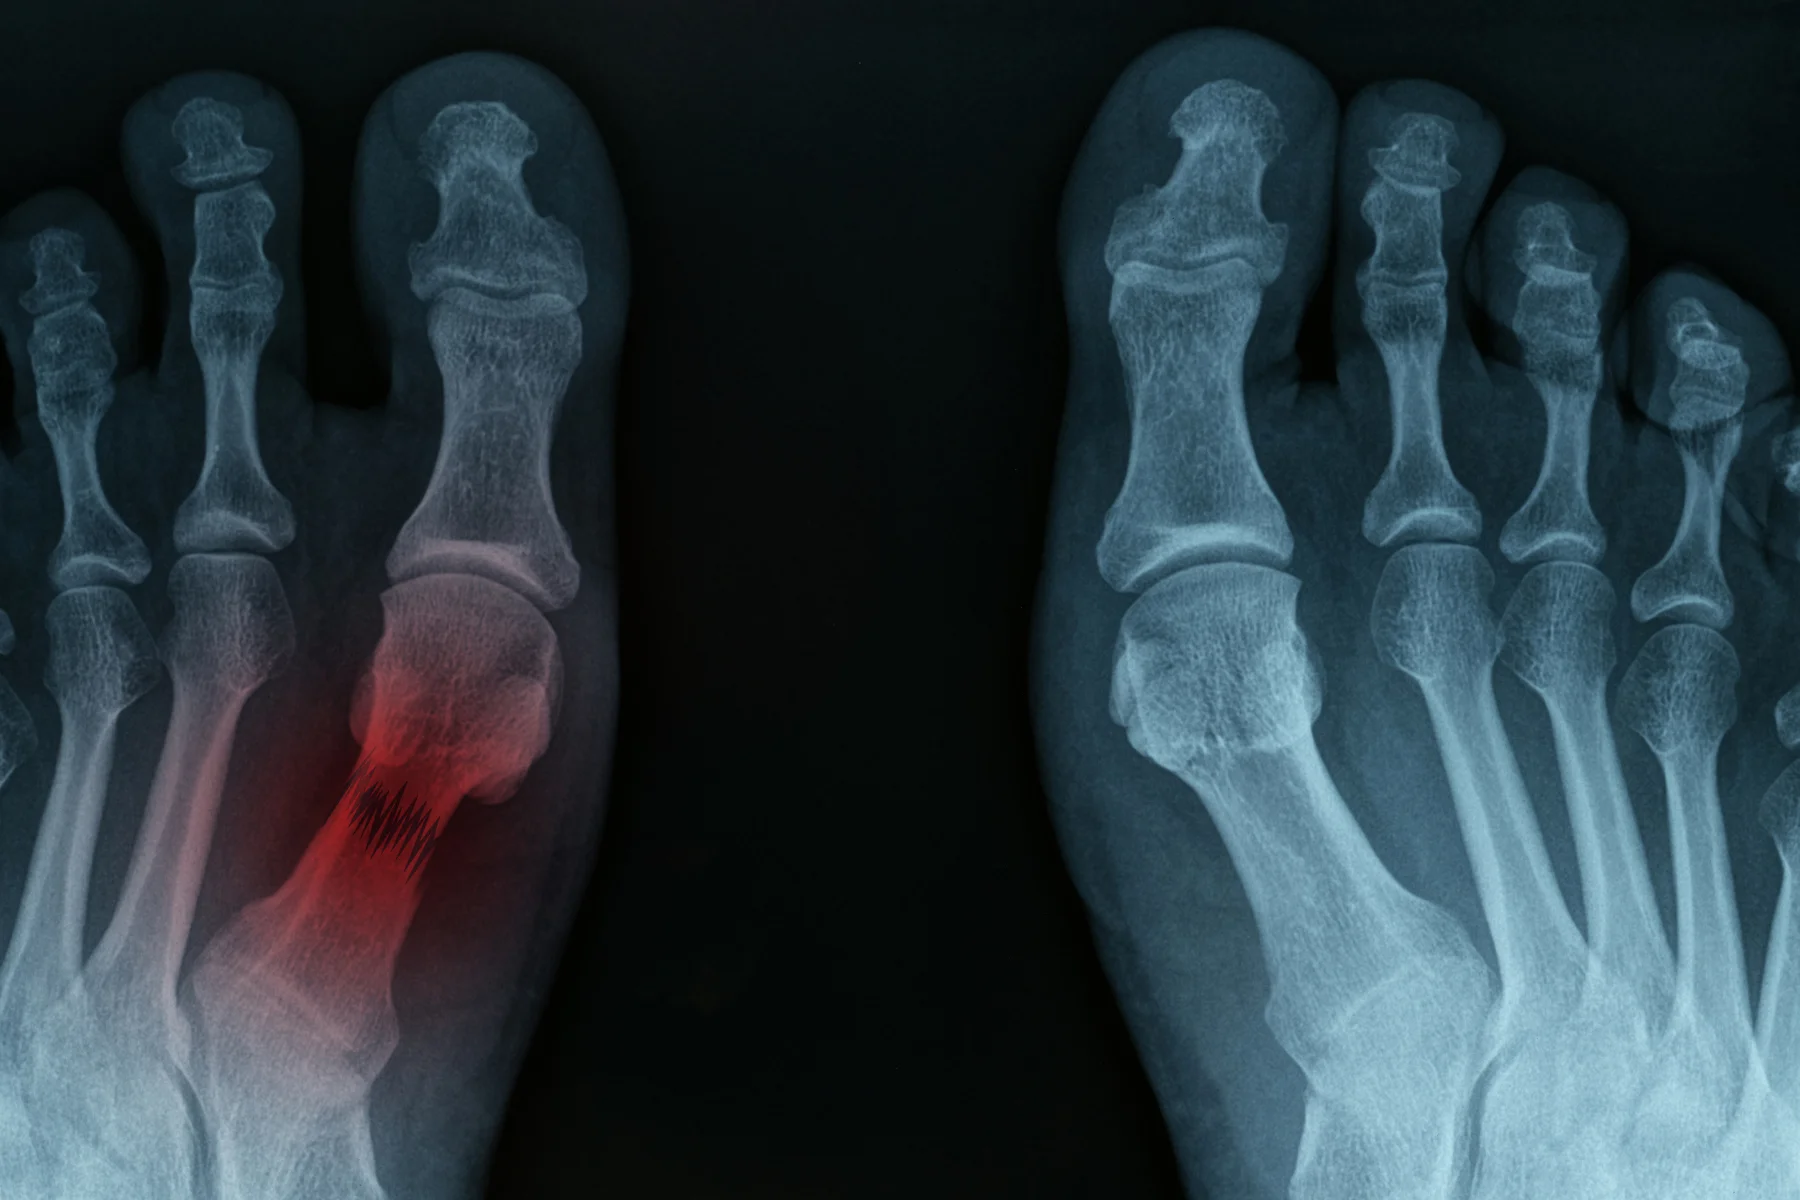

Stress Fracture

Stress fractures are tiny, hairline breaks that can occur in the bones of the foot. They can be caused by overtraining or overuse, improper training habits, training surfaces, improper shoes, flatfoot or other foot deformities, and even osteoporosis. These tiny breaks in the bones of the feet can lead to a complete break if left untreated.

Stress fractures commonly occur in the metatarsal bones of the feet, the tibia (shin bone), navicular and femur (thigh bone). Some symptoms of a stress fracture may include pain and swelling, particularly with weight bearing on the injured bone. Some other symptoms associated with stress fractures include;

A comprehensive podiatric assessment is recommended to prevent the progression of symptoms and ensure appropriate treatment is undertaken. Diagnostic imaging including a X-ray is used to diagnose a stress fracture. In some cases the fracture may not show up on the X-ray until a couple weeks after the pain starts. Patients are advised to temporarily stop activities that cause the stress fracture during the six to eight weeks it may take for the fracture to heal.